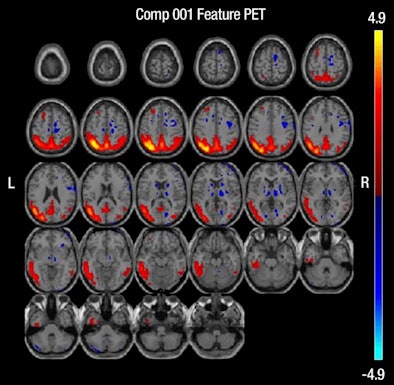

| MR images above highlight in red the bilateral medial temporal lobes, inferior and lateral temporal lobes, and anterior and inferior frontal lobes, consistent with atrophy in brain regions of people who develop Alzheimer's. In blue are negative signals in the periventricular white matter, consistent with higher levels of white-matter disease in those same patients. Below are FDG-PET images in which red areas show the temporoparietal lobes (right greater than left) and the posterior cingulate region, consistent with hypometabolism in the brain regions of patients who progress to Alzheimer's. Images courtesy of Radiology. |